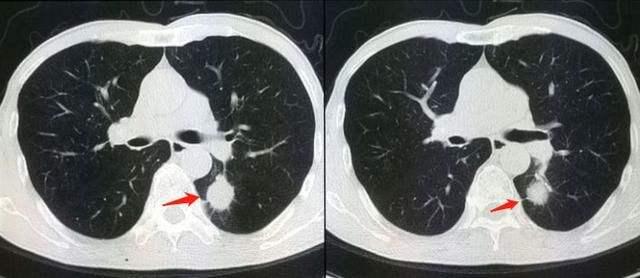

肺部的CT,可以检查两侧的肺部、气管和胸膜有没有异常,例如肺炎,肺部结节,肺癌,肺脓肿,肺大疱,气胸,胸腔积液,胸膜炎,肺结核,支气管扩张等等。几乎所有的肺部疾病,都可以通过肺部CT发现。其实,胸部CT还可以看有没有淋巴结转移,包括肺部的淋巴结和纵膈的淋巴结。

肺癌